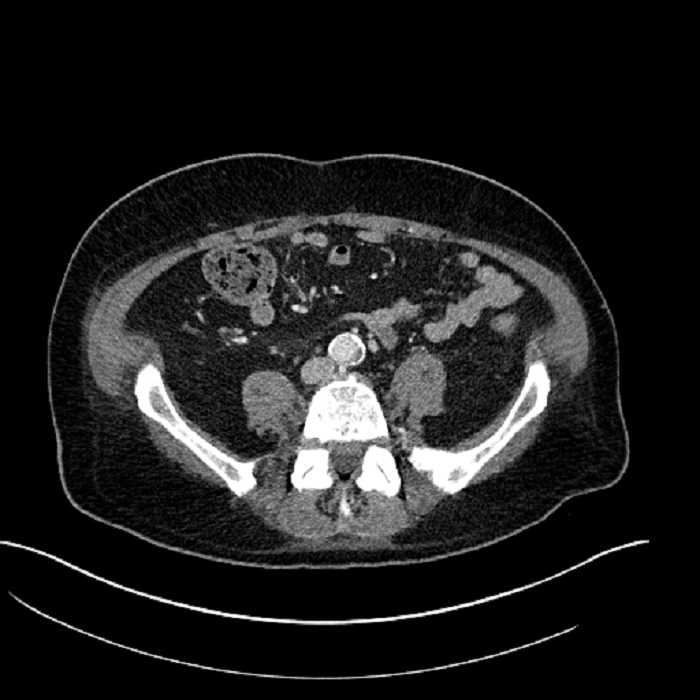

• Mild mural thickening of a segment of the sigmoid colon with adjacent fat stranding and a 1.5 cm fluid and gas collection along the tip of an inflamed diverticulum

• Loss of the normal fat plane between this collection and adjacent loops of small bowel, which demonstrate mural thickening

• High grade stenosis of the left common iliac artery, with the left internal and external iliac arteries remaining patent

Acute sigmoid diverticulitis complicated by a small contained perforation and a large abscess in the right hepatic lobe. Additional small subcapsular abscesses along the anterior margin of the left hepatic lobe.

Additionally, loss of the normal fat plane between the peridiverticular collection and adjacent thickened loops of small bowel raises the potential for an enterocolonic fistula.

High grade stenosis of the left common iliac artery. The left external and internal iliac arteries are patent.

Hepatic abscess showing the double target sign with low density internally surrounded by a thin inner enhancing rim (red arrow) and ill-defined outer low density rim (yellow arrow). Blue arrow indicates an internal septation. Red arrows: additional smaller subcapsular abscesses. Red arrow: focal contained perforation associated with diverticulitis.